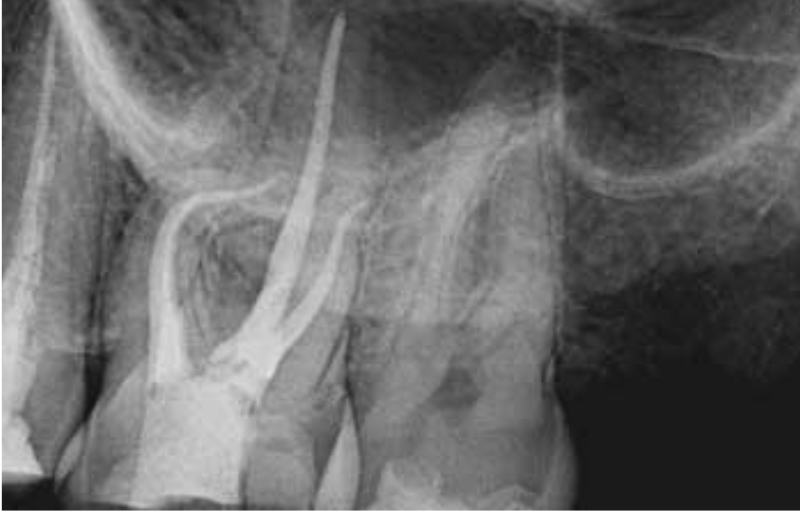

Root Canal Treatment

Root canal treatment is most commonly a painless procedure that will preserve your tooth and keep the structure from getting more damaged due to infection and trauma.

In a nutshell, a root canal is actually your tooth's savior. The name itself implies that it is a treatment of the roots of the tooth, and more specifically in the canal portion of the root where the nerve, blood vessels, and connective tissue reside.

A root canal treatment is performed when your tooth is badly decayed and is touching the canals of the root. This can be very painful or sometimes painless too. RCT is also performed on a traumatised/fractured tooth which may or may not be decayed.

The procedure is done under local anaesthesia after which it becomes completely painless. The dentist removes all the decayed part, cleans the canals thoroughly using advanced rotary instruments and apex locators, and finally fills the canals with gutta-percha, dental cement, and seals it with a crown.